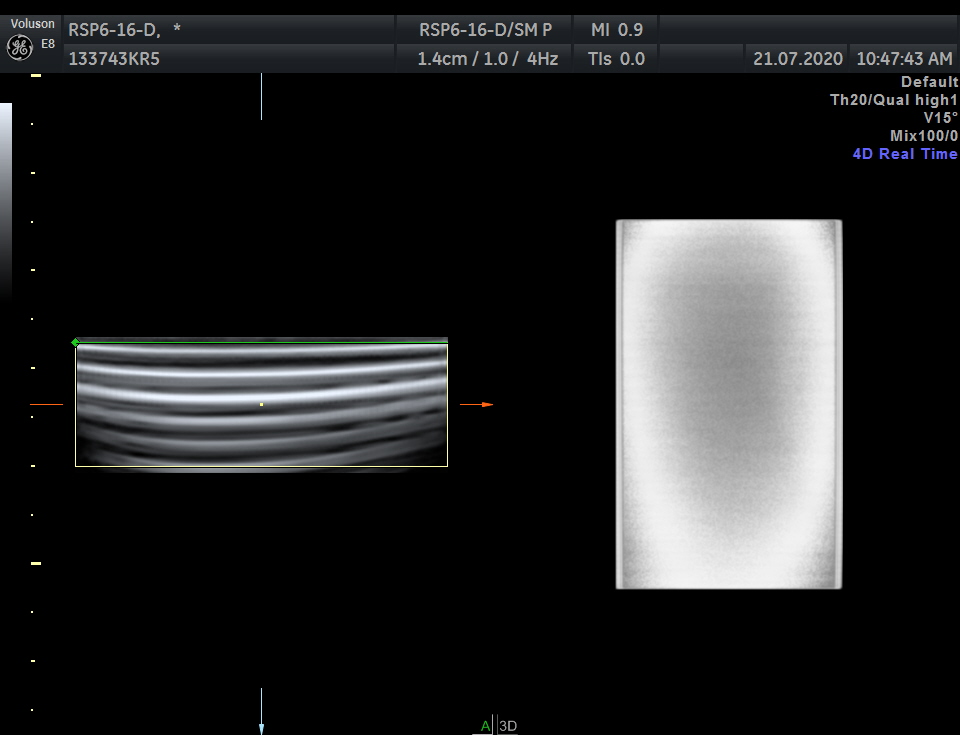

Breast, Small parts, Vascular and Musculoskeletal

Frequency Range: 18 – 6 MHz

GE RSP6-16-D 3D/4D Linear for Breast, Small parts, Vascular and Musculoskeletal

| Type of examination 3D/4D | |